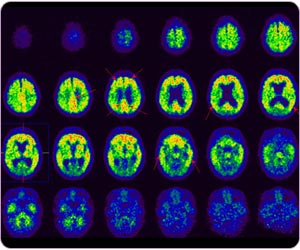

Region-based quantitative analysis for C-11 PIB brain study

C-11 PIB PET detects typical Alzheimer's disease with amyloid plaque at post cingulate gyrus, frontal lobe, precuneus, parietal lobe and temporal lobe.